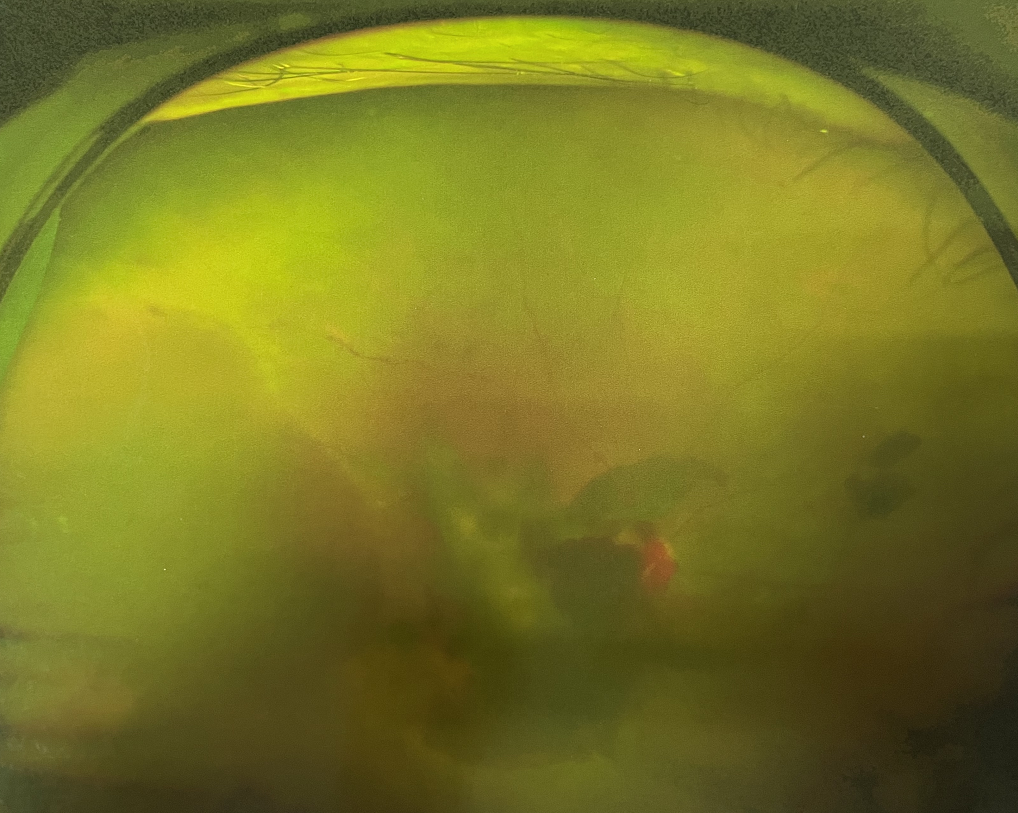

眼底出血

1、眼底出血

高血壓、糖尿病、動脈粥樣硬化、高度近視、視網(wǎng)膜中央靜脈阻塞、脈絡膜新生血管性疾病等都可能造成眼底出血,引起中心視力下降、視物變形、黑影飄動、飛蚊癥、閃光感等癥狀。